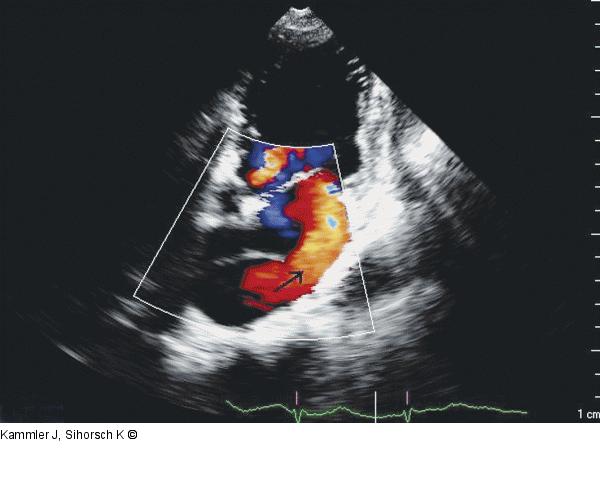

Abbildung 5: Echo Farbdoppler im Vierkammerblick. Pfeil in Richtung der lateral gelegenen Penetration in der Membran im linken Vorhof. |

Farbdoppler im Vierkammerblick. Pfeil in Richtung der lateral gelegenen Penetration in der Membran im linken Vorhof. |